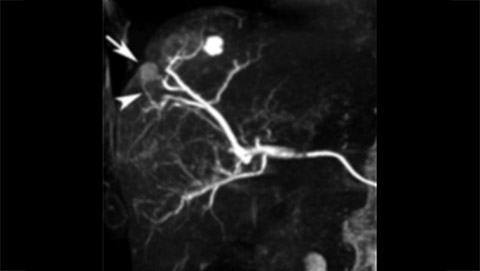

Live 3D MR/CT Roadmap fuses live 2D fluoroscopy on a pre-acquired MR or CT image, which may reveal hidden anomalies and enable real-time motion compensated navigation to support interventional procedures. Live 3D MR/CT Roadmap provides full 3D view for guidance of guidewires, catheters and coils through complex vessel and anatomical structures.

Dynamic 3D Roadmap provides a sustainable 3D roadmap to support interventional procedures. Dynamic 3D Roadmap matches the real-time 2D fluoroscopy images with the 3D-RA reconstruction of the vessel tree. It provides a 3D real-time insight of the advancement of the guide wire, catheter and coils through complex vessel structures. The Unsubtracted 3D Roadmap option reduces subtraction artifacts caused by patient breathing and movements, providing a clear roadmap during abdominal and thoracic interventions.

Live 3D Roadmap allows you to follow the advancement of guidewires, catheters and coils in real-time. It automatically adapts in real-time to changes in C-arm angulation and rotation, table movement, field of view and source-image distance.

High-resolution 3D-RA vascular images or previously acquired 3D segmented MRA or CTA data is registered to the current patient position through a low X-ray dose 3D-RA scan, allowing ‘re-use’ of contrast and X-ray doses.